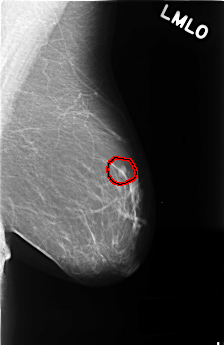

C_0382_1.LEFT_MLO

LEFT_MLO LINES 4480 PIXELS_PER_LINE 2904 BITS_PER_PIXEL 12 RESOLUTION 50 OVERLAY

FILE: C_0382_1.LEFT_MLO.OVERLAY

TOTAL_ABNORMALITIES 1

ABNORMALITY 1

LESION_TYPE MASS SHAPE OVAL MARGINS CIRCUMSCRIBED

ASSESSMENT 3

SUBTLETY 5

PATHOLOGY BENIGN

TOTAL_OUTLINES 1

BOUNDARY